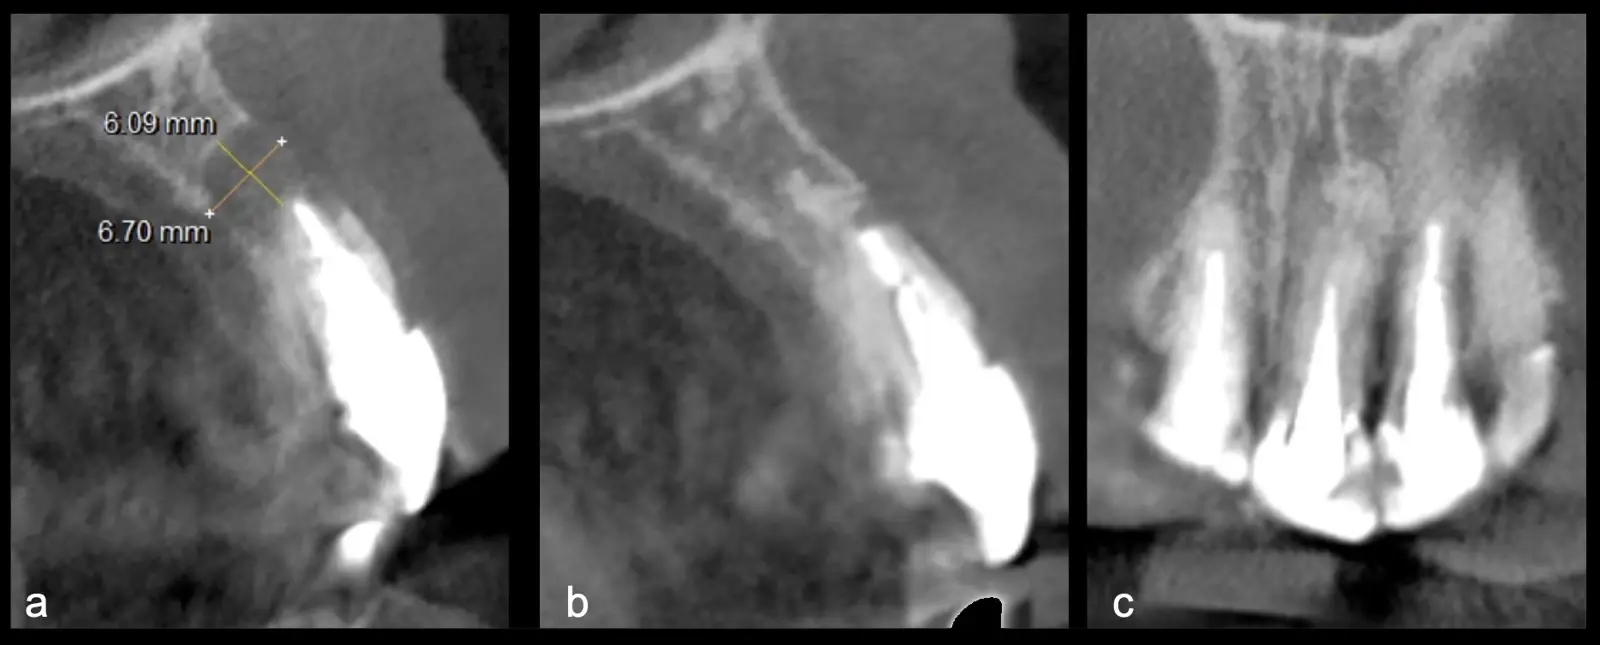

Figura 24. Vista sagital TCCB pieza 2.1. Preoperatorio: imagen hipodensa de 6 mm de diámetro con osteólisis y pérdida de tabla vestibular y palatina (a). Control a los 3 años: imagen hiperdensa compatible con zona regenerada a nivel apical, con presencia de cortical palatina y vestibular (b). Vista coronal TCCB pieza 2.1 control a los 3 años: imagen hiperdensa compatible con hueso en proceso de reparación, presencia de cortical palatina y vestibular (c).